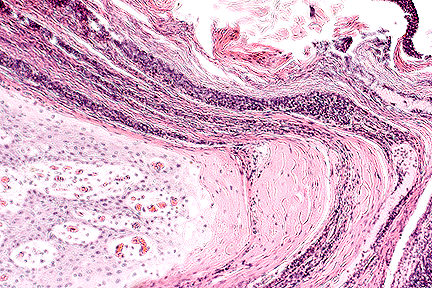

Alternating bands of keratin and inflammatory cells characteristic of dermatophilosis (10X, HE, 110K)

The surface of the lesion is composed of alternating layers of predominantly parakeratotic hyperkeratosis with dense bands of degenerating neutrophils. Epidermal changes are qualitatively similar in both follicular and interfollicular epidermis but are more marked in the follicular canals. The changes include pseudoepitheliomatous acanthosis, marked vacuolar degeneration of keratinocytes, neutrophil exocytosis and the formation of several, varying sized superficial pustules. Numerous gram positive filamentous hyphae with a characteristic railroad track appearance are present within the superficial crust particularly within the hair follicle ostia. Superficial foci of keratinocyte reticular degeneration which exhibit positive immunostaining for orf virus antigen are present in some sections.

Superficial dermal vessels are congested and many are plugged with neutrophils. The dermis in the immediate subepidermal area is edematous and diffusely infiltrated by large numbers of neutrophils, lymphocytes, plasma cells and macrophages. Deeper in the dermis the inflammatory cell aggregates and the edema are largely confined to angiocentric and periadnexal locations.

The main source of infection in dermatophilosis is infected animals including healthy carriers. The two most important predisposing factors in the development of lesions are excessive wetting and skin damage. Excessive moisture activates latent zoospores and can also interfere with epidermal defense mechanisms. Once the zoospores have germinated the branching filaments extend through the damaged epidermis particularly in the hair follicles. An intense inflammatory response is stimulated and this inhibits deeper penetration by the bacteria. The underlying damaged epidermis rapidly regenerates and premature keratinization is stimulated. Bacteria from reservoirs in the hair follicles invade the newly regenerated epidermis and another burst of acute inflammation is stimulated. These cyclic events result in the formation of the characteristic palisading crust.

AFIP Diagnosis: Haired skin: Dermatitis, proliferative, chronic-active, diffuse, severe, with parakeratosis, corneal microabscesses, folliculitis, ballooning degeneration, numerous filaments of paired cocci, and eosinophilic intracytoplasmic inclusions, etiologies consistent with Dermatophilus congolensis and ovine parapoxvirus, black-faced mountain cross, ovine.